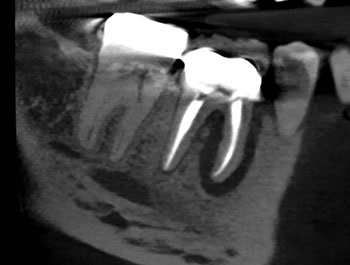

Fig. 2: Postoperative PA.

The patient returned in three months, when resolution of symptoms, healing of the deep probing defect and bone regeneration were confirmed. The tooth was obturated, and a foundational restoration was placed before the rubber dam was removed. Fourteen years of follow-up confirmed long-term periradicular health. The amount of appreciation and gratitude that this patient expressed reminds us that each individual tooth demands our best efforts.